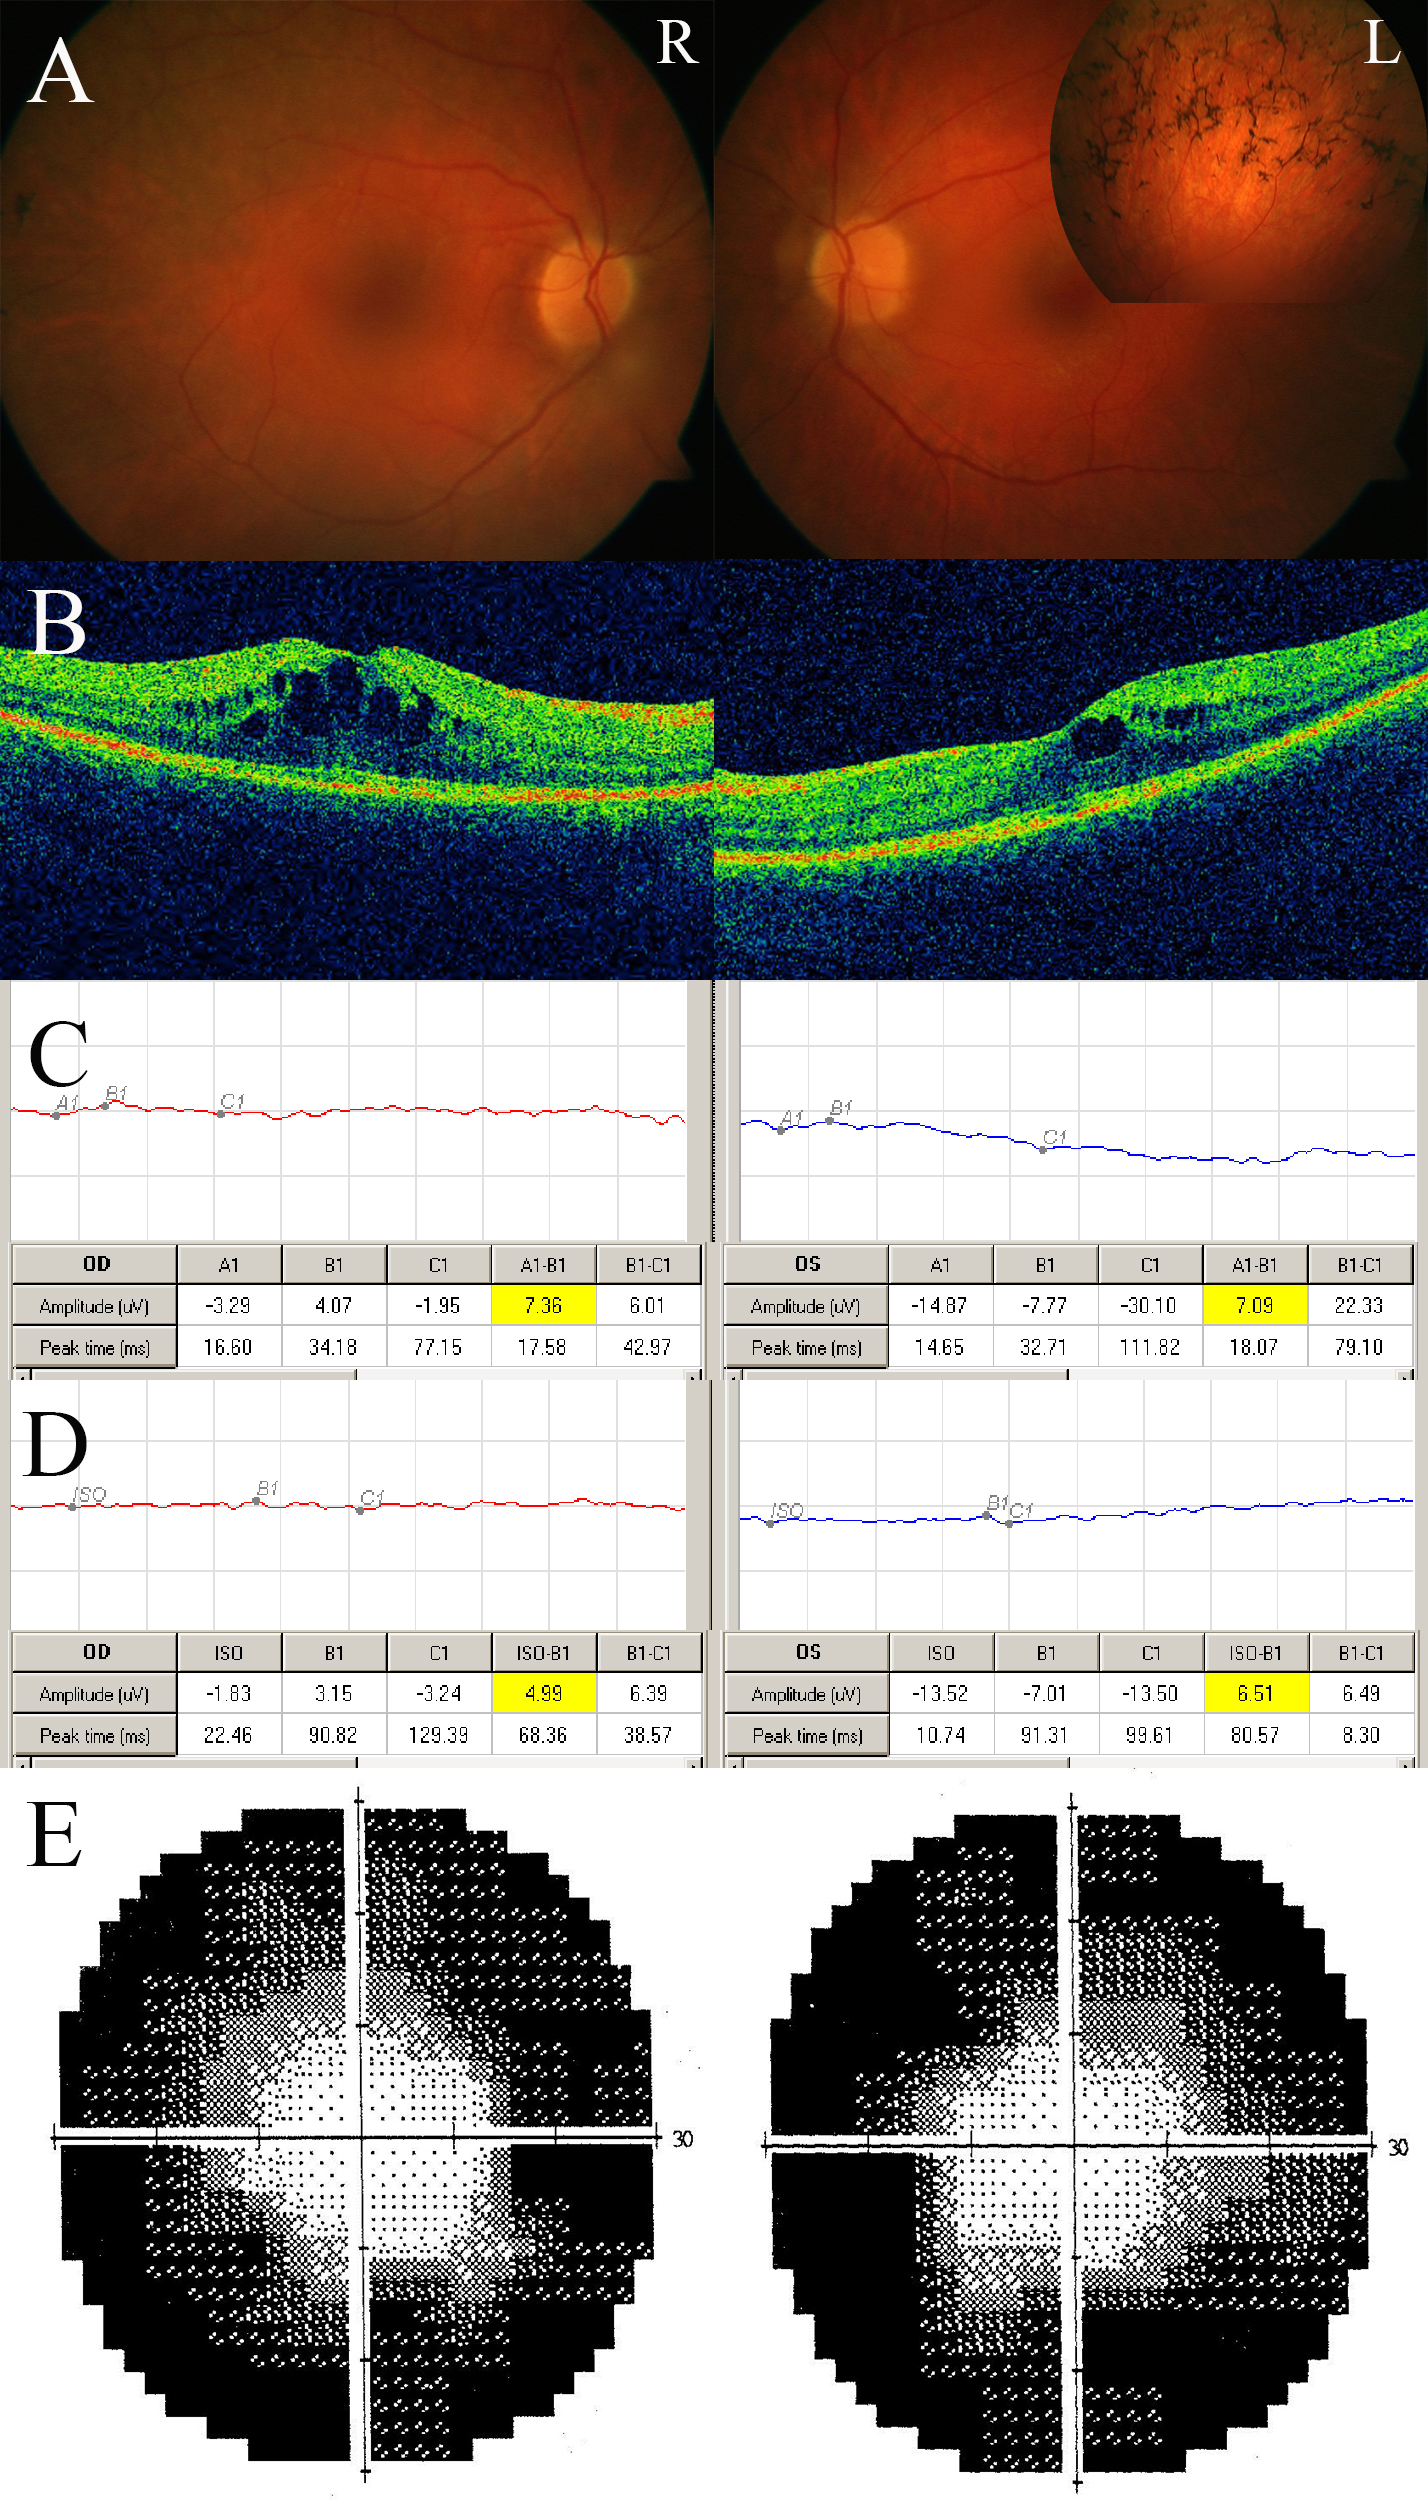

Figure 4. Clinical case of a patient carrying an USH2A missense variants (c.1434G>C (p.Glu478Asp), c.7595–2144A>G (p.Lys2532Thrfs*56)) on one allele and an USH2A exon deletion (Del EX22) on the other allele (patient BL). A: Fundus photographs: typical form of retinitis pigmentosa. B: OCT scans: cystoid macular edema. C: Photopic electrophysiological responses: severely abnormal. D: Scotopic electrophysiological responses: severely abnormal. E: Humphrey visual field: concentrically reduced. This patient carrying a monoallelic USH2A deletion presented with the clinical picture of typical retinitis pigmentosa, similar to other cases in our series.